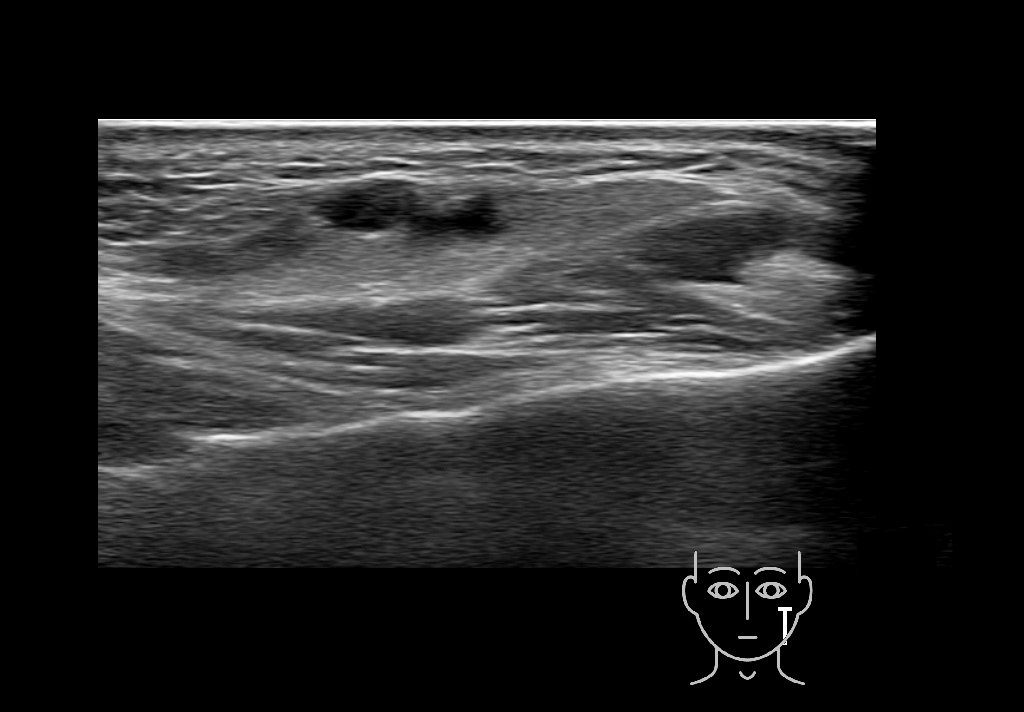

Filler injections in the parotid gland may go unnoticed, however, inflammatory reactions and abscesses may occur. Hypervascularity can be seen with color doppler. Filler deposits are supposed to be injected into the superficial fatty layer . The space to inject into this layer may be limited. Routinely we measure a width of 2-4 millimeters with sometimes subcutaneous layers being less than one millimeter thick.

Hover over an image to view the secondary image or click on the image title for more information.